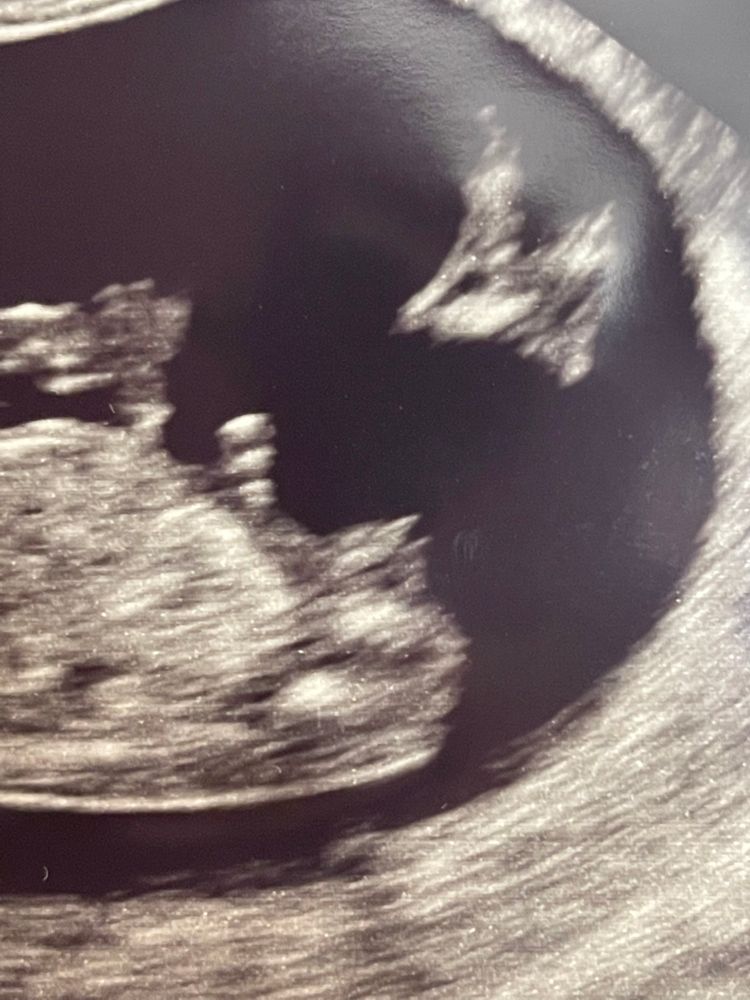

Девочка💗или мальчик💙?

Вроде мальчишка. Ну или хитрая девчонка, которая захватила ножками пуповину. Но больше склоняюсь к тому что там прячется мальчишка)

Если это бугорок, то и ни туда и ни сюда как то 😂 мальчик думаю больше похож

Не уж-то пацан?)))) Надеюсь, это не пуповина))

Женевьева, блин, вот не понятно. Бугорочка не видно чётко. Он белее обычно на узи( а есть ещё фото?)))

Если я туда смотрю, то вроде девочка🙂

Алиса, тоже самое хотела написать, если я правильно нашла половой бугорок, то он немного наклоне, а это вроде девочка, т. к у мальчиков более перпендикулярно.. Интересно, а что доктор сказал😊